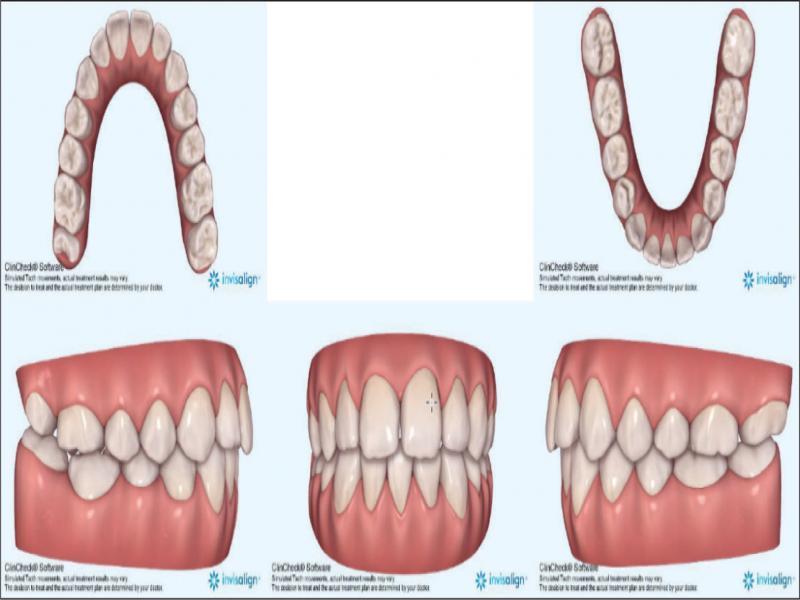

With these considerations, it was planned to treat the patient by the extraction of the lower right central incisor (41), by transverse dental arch expansion, and the management of the vertical relationships by avoiding mechanics that would tend to extrude posterior teeth. The 41 was chosen for extraction as it allowed for alignment of the remaining lower incisors, largely through mesial crown tip. In addition, there was slightly less gingival attachment on 41 and the tooth had a small incisal fracture. The extraction of 31 would perhaps have been more advantageous for the alignment of 32 but would have necessitated a more challenging bodily translation of 41 rather than mainly mesial crown tip. It was considered that clear aligner therapy would be beneficial from a vertical perspective, by minimising the extrusive mechanics inherent to fixed appliances. Figure 4 shows the prescribed finishing position of the dentition. Vertical control was augmented by the placement of occlusal bite pads in the aligners themselves on the occlusal of the molars in both arches to provide a bite-plane effect posteriorly (Figure 5). Furthermore, the absence of fixed appliances serving as a predisposing factor is favourable in managing concerns regarding the patient’s oral hygiene and cariogenic dietary intake.

Invisalign® predicted treatment outcome.